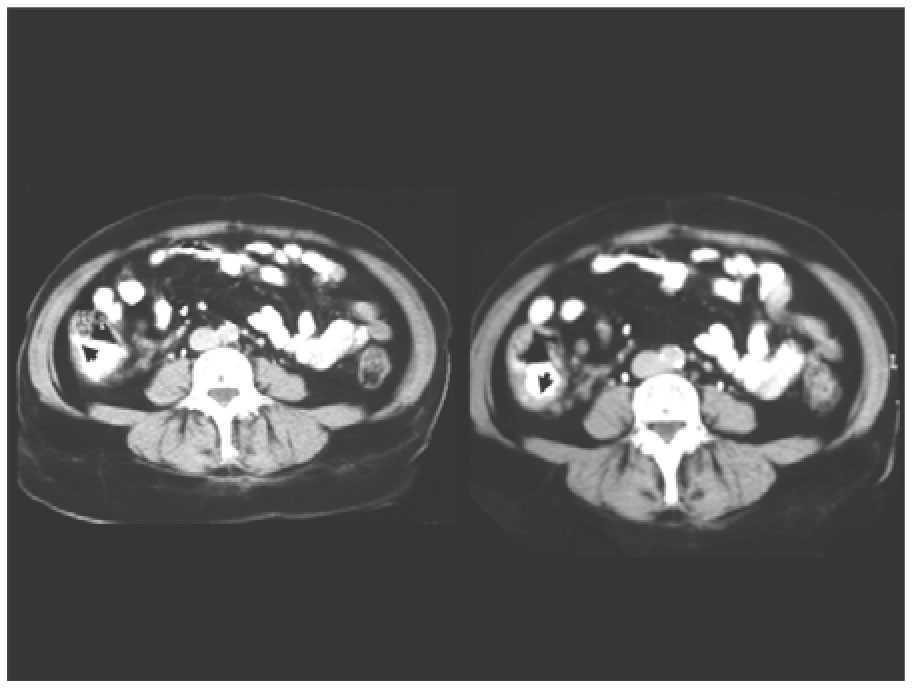

This is a 52 years old, Mexican-mestizo female, presented to our gastrointestinal emergency unit with a history of a week right lower quadrant abdominal pain, intermittent fever, bloating, tenesmus and mucus discharge in the stools. She had experienced a three kilograme weight loss in the previous four months, associated with an episode of acute bloody diarrhea which was self-medicated. Abdominal examination was soft, with palpable mass and tenderness in right lower-quadrant. No peritoneal signs were documented. Laboratory exams were unremarkable. Contrast-enhanced tomography (CT) revealed a concentric thickening (22 mm) of the cecum wall (Figure 1). The liver, spleen and pancreas were normal. Given the results of CT scan (concentric thickening and mass-like appearance on the cecum wall) a preliminary diagnosis of colon cancer was made. A colonoscopy was performed and showed a bulky-ulcerated mass in the cecum area. Multiple "flask-shaped" ulcers were documented on the surrounding mucosa and several endoscopic biopsies were taken. On histological examination, the presence of multiple crypt abscesses and superficial ulcerations were identified. In addition, amebic trophozoites were documented within the exudative tissue. Numerous phagocyted red blood cells, which are characteristic of EH, were contained within the trophozoites (Figure 2). Subsequent laboratory parameters also revealed positive anti-amoebic antibodies (titles of 1:512).

¿ Figure 1. Double contrast CT scan of the abdomen showing an irregular concentric mass on the cecal wall (large arrows) partially compressing the terminal ileum.

Contrast-enhanced tomography and colonos-copy are sensitive tools for the workshop of differential diagnosis of a cecal mass. Endoscopic evaluation can yield a definitive diagnosis in about 66% of cases.9 The most relevant CT findings are ileocecal tumor and partial or concentric thickening of the colonic wall. Furthermore, CT scan can help detect spread lesions to other organs.12